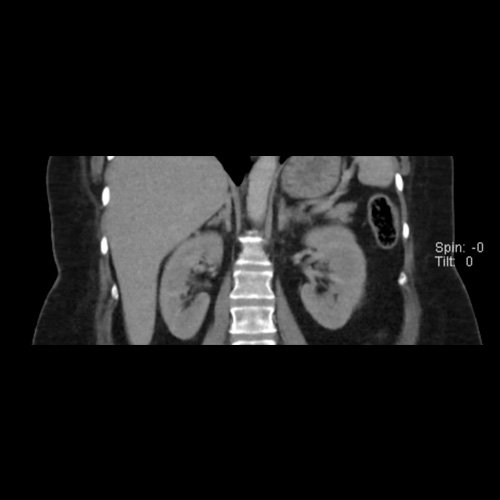

Tomografía de abdomen y pelvis sin contraste oral con contraste EV (12/02/26): El hígado es de forma, tamaño y situación habituales. Su superficie es lisa, y sus bordes son agudos. Imagen hipovascular aislada de 15 mm en segmento V de aspecto inespecífico. Sugiero complementar con RMI. La vía biliar intra y extrahepática es de calibre conservado. La vesícula biliar es de forma, tamaño y situación normales, sin imágenes que sugieran la presencia de litiasis. Tener en cuenta que este método puede pasar por alto litiasis colesterínicas. El bazo es de forma, tamaño y situación normales. El páncreas es de características normales. El conducto de Wirsung es de calibre conservado. Adenoma adrenal izquierdo de 16 mm. Ambos riñones son de forma, tamaño y situación habituales. Concentran y eliminan adecuadamente la sustancia de contraste. Sin evidencia de alteraciones calicopiélicas ni ureterales. La aorta, las arterias ilíacas primitivas, internas, externas y femorales, son de calibre y trayecto conservado, permeables. La vena cava inferior y las venas ilíacas primitivas, internas, externas y femorales son de calibre y trayectoria conservados, permeables. No se observan adenomegalias intraperitoneales, retroperitoneales, ilíacas ni inguinales. No se observan alteraciones a nivel del tracto gastrointestinal. La vejiga es de paredes lisas, sin presentar efectos de masa endoluminales ni parietales. Utero en AVF, lateralizado a izquierda. Pequeña hernia umbilical de contenido graso y escaso líquido intrasacro. No se identifican alteraciones en las estructuras óseas visualizadas.

TC de abdomen y pelvis con contraste endovenoso (12/02/2026) Corte coronal: hígado de forma, tamaño y situación habituales, con superficie lisa y bordes agudos. Imagen hipovascular aislada de 15 mm en segmento V de aspecto inespecífico.

TC de abdomen y pelvis con contraste endovenoso (12/02/2026) Corte coronal: adenoma adrenal izquierdo de 16 mm.